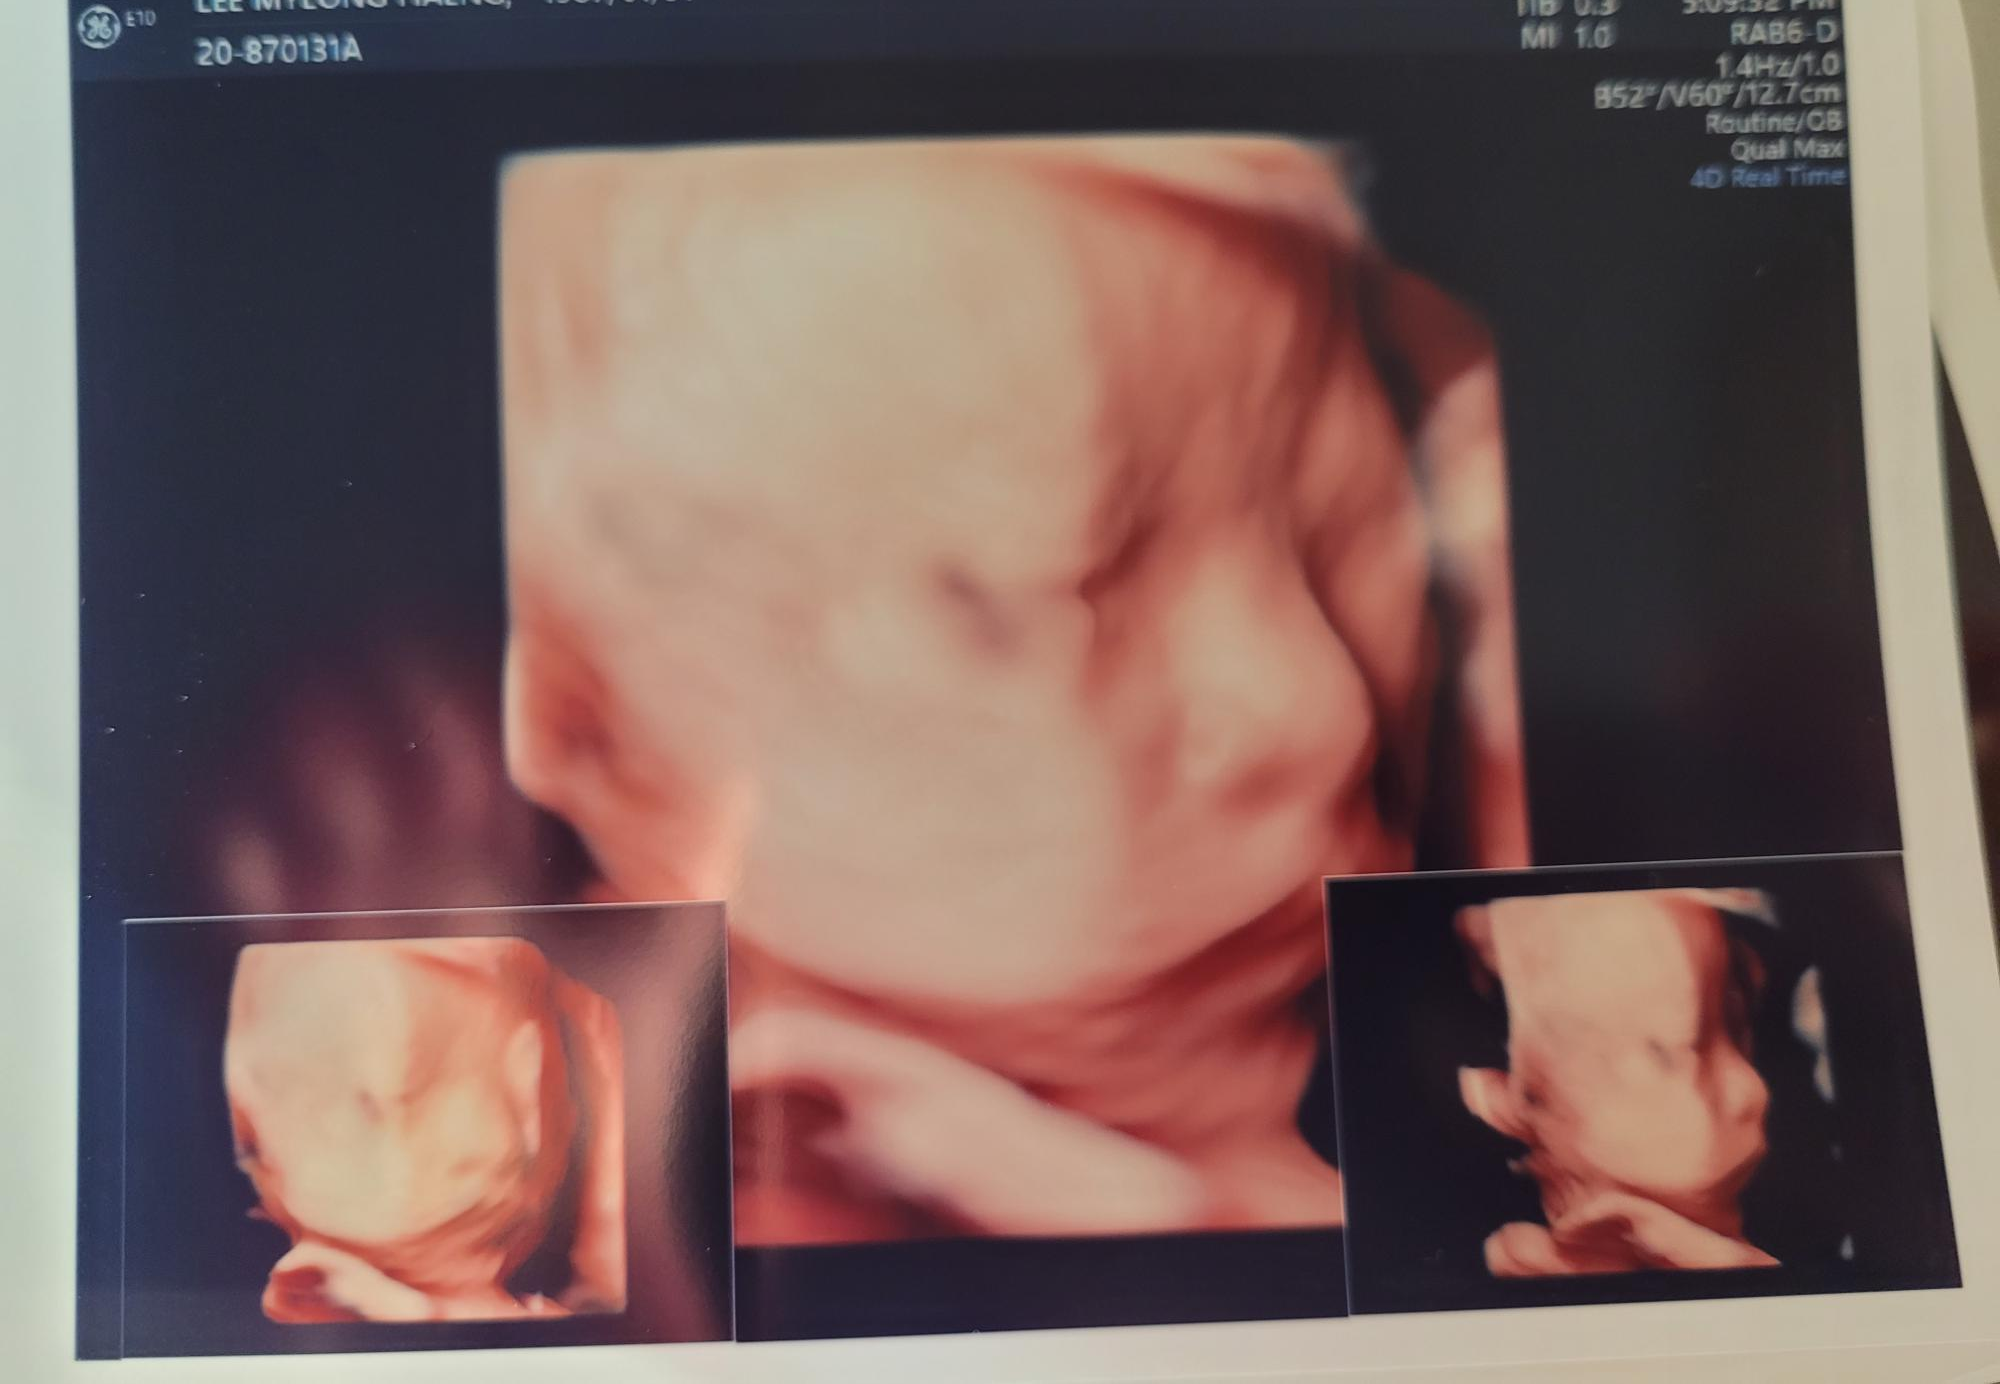

봄빛병원 입체초음파 후기 / 비용

봄빛병원 입체초음파 비용은 5만원입니다.

접수할때 바로 수납까지하고요. 만약 여러번 시도했는데도 얼굴을 못봤을경우 환불은 안된다고합니다.

저는 첫째아이이고, 넘 궁금했기때문에 하길 잘 한거같아요..ㅎㅎ